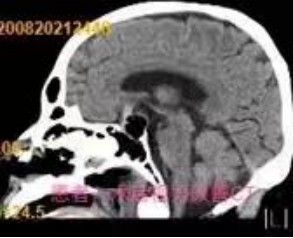

近段时间,自贡四院神经外科收治了几名垂体瘤患者,这几名患者的首要临床表现都是出现视物模糊,看东西重影,第一时间到眼科检查发现不是眼睛的问题,而是颅内垂体长了肿瘤。自贡四院神经外科的医生通过在神经内镜下经蝶鞍区将垂体瘤切除后,患者视力改善,恢复良好。

垂体瘤症状主要分为垂体瘤压迫产生的相关症状和激素分泌异常两个部分。因垂体瘤压迫,患者可表现为头痛、视力减退、视野缺损、尿崩、垂体卒中等。激素分泌异常常见于功能性垂体瘤,可表现为相应激素的分泌过多或减少。垂体瘤手术有开颅和微创两种方法。其中,在神经内经下经蝶窦手术采用的微创方法,是目前垂体瘤治疗的主流方式。神经内镜是神经外科一种非常重要的先进技术,内镜使得手术切口更小,脑组织造瘘范围更局限。自贡四院神经外科拥有高清神经内镜设备,有神经内镜专业组,对内镜辅助下的微创手术技术熟练,造福了很多颅脑肿瘤患者。